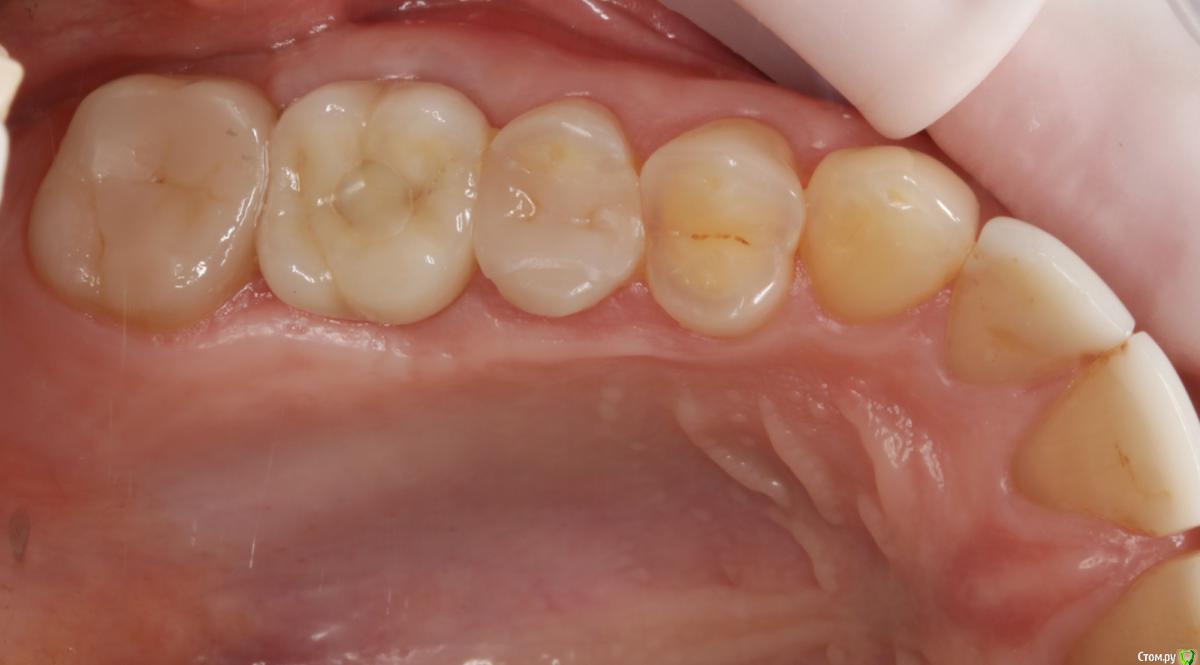

Dmitry DK Опубликовано 10 сентября, 2019 Поделиться Опубликовано 10 сентября, 2019 Фотопротокол к сожалению не полный, но ничего особенного и не проводилось. 1) Открытый синус, удален пломбировочный материал из пазухи, уложен 1 г Bio-oss 2) через 6 мес имплантация Straumann SP 4.1\10 Результат через год 9 Ссылка на комментарий